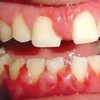

ANUG (äge nekrotiseeruv haavandiline gingiviit/parodontiit)

Äge nekrotiseeruv haavandiline gingiviit (ANUG) või nekrootiline haavandiline gingiviit (NUG) on nekrootiline bakterite poolt põhjustatud infektsioosne igeme haigus, mille korral põletikust on haaratud hammast ümbritsev ige ja kahjustus ei ulatu...